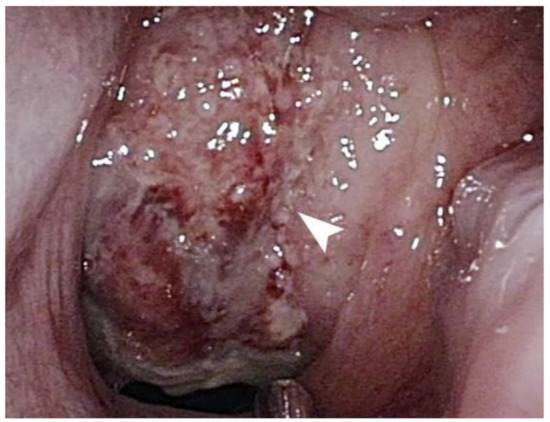

2. Case Presentation